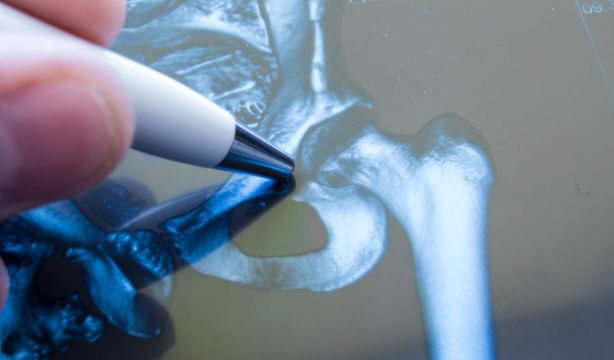

Una de las zonas más afectadas es la cadera. Según OrthoInfo: "Es una de las articulaciones más grandes del cuerpo. Es un tipo de 'enartrosis': está formada por una bola y una cavidad. La cavidad está formada por el acetábulo, que es parte del hueso grande de la pelvis. La bola es la cabeza femoral, que es el extremo superior del fémur. Las superficies óseas de la bola y la cavidad están cubiertas de cartílago articular, una sustancia suave y resbaladiza que protege y amortigua los huesos y les permite moverse con facilidad".

La operación consiste en sustituir las partes dañadas de la articulación de la cadera, compuesta por la cabeza del fémur y el acetábulo, la parte de la pelvis, por una artificial (prótesis o implante). "Estos componentes se articulan entre sí mediante unas superficies de cerámica de bajo desgaste, de metal o de polietileno, lo que se llama par de fricción. Cuanto menor sea el desgaste o mejor sea el par de fricción, más tiempo durará la prótesis. Las prótesis pueden ser cementadas (permiten la fijación de la prótesis al hueso del paciente inmediatamente. Se emplean en pacientes mayores, con hueso de mala calidad), o no cementadas, en que el hueso del paciente va a incorporar o crecer en la superficie de la prótesis", aclara.